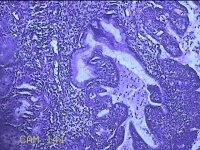

性别

女

年龄

36岁

临床诊断

宫颈赘生物

一般病史

发现宫颈赘生物1个月。

标本名称

大体所见

灰白暗红色肿物1x0.7x0.2cm一个,表面糜烂。

图1